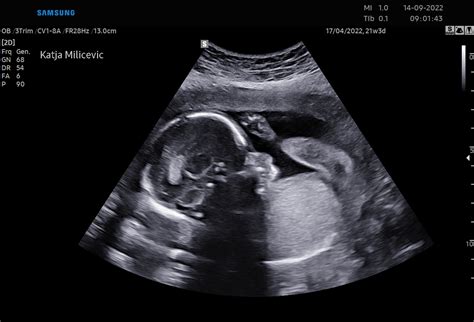

V 30. tednu nosečnosti plod običajno tehta med 1200 in 1400 grami, njegova dolžina pa znaša približno 39 centimetrov. Trenutna teža 1350 gramov pri 30 tednih nosečnosti, kot jo navajate, ni problematična in spada v pričakovane okvire. V tem tednu se količina maščobnega tkiva ploda povečuje, kar pripomore k bolj zaokroženi telesni strukturi. Podkožna maščoba, ki se nahaja tik pod kožo, je bogata z drobnimi kapilarami, ki kožo oskrbujejo s krvjo in hranili. V maternici se volumen plodovnice sicer zmanjšuje, saj plod postaja vse večji in zavzema več prostora, vendar je še vedno dovolj, da se plod lahko premika, čeprav so njegovi gibi lahko manj intenzivni zaradi omejenega prostora.

- Tretji trimester (27.-40. teden): Plod intenzivno pridobiva na teži in rasti. V 28. tednu plod doseže težo okoli 1000 g. V 30. tednu plod tehta med 1200 in 1400 g. V 32. tednu plod tehta med 1600 in 1800 g. V 35. tednu so jetra, ledvice in pljuča popolnoma pripravljeni za izvenmaternično življenje. V 37. tednu je plod že donošen in se počasi spušča v medenico. V 38. tednu dolžina ploda običajno ne rasteta več, teža pa znaša okoli 3100 g.

Tabela rasti ploda prikazuje povprečne vrednosti za posamezne tedne nosečnosti. V 30. tednu nosečnosti je povprečna masa ploda po teh podatkih 1319 gramov. Vaša trenutna teža ploda 1350 gramov je nekoliko nad tem povprečjem, kar pa ne pomeni nujno težav, še posebej ob upoštevanju nosečniškega diabetesa, ki lahko vpliva na rast.